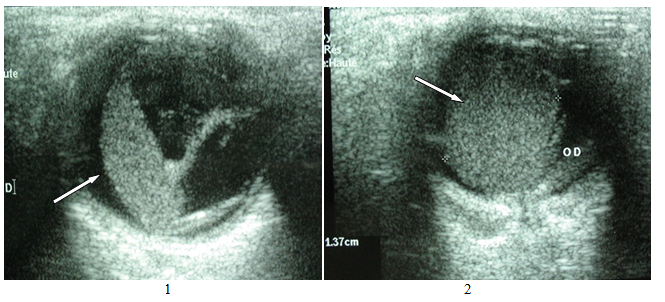

Figure 1&2 Ocular B ultrasonography in transocular sections: right choroidal tumor in lateral (1) and front (2) view with a diameter of 1.37 cm.

A 38-year-old patient, with no notable pathological history, presented for a progressive decrease in visual acuity of the right eye that had been evolving for two weeks and had been brutally aggravated in the last two days. Ophthalmological examination with fundus showed serous and extensive detachment of the right retina with sub-retinal infiltrates on both sides. B-mode oculo-orbital ultrasonography with a high-frequency probe showed the presence of well-defined echogenic formations of homogeneous choroidal and bilateral tissue echo- structure (Figure 1-3) suggestive of metastases. The exploration was completed by oculo-orbital magnetic resonance imaging confirming the same findings. The search for the primitive objectified a left breast carcinoma. She had a hard, irregular nodule two centimeters from the supero-outer quadrant of the left breast. Echo-mammography showed stellar nodular opacity at the left supero-external quadrant measuring two centimeters and containing micro-calcifications. This opacity was rated ACR 4 (American College of Radiology) and highly suspect. The CA15-3 level was elevated to 85 IU / ml (normal <35 IU/ml) and the nodule cyto-puncture found infiltrating ductal adenocarcinoma with trabecular carcinomatous cells, pleomorphic nuclei, marked atypia, and many mitoses; grade III SBR (histo-prognosis grade of Scarff Bloom and Richardson). There were no associated axillary lymphadenopathies, neither homo nor contralateral. Extension assessment for other metastases was negative (abdominal ultrasound, standard chest X-ray, thoraco abdominal CT scan, brain MRI and bone scintigraphy). The patient was given immediate radiotherapy for secondary ocular lesions given the visual risk. After four courses of radiotherapy, the evolution was unfavorable with worsening of the visual deficit and persistence of choroidal metastases unchanged on the control ultrasound done a month later. Surgery for breast cancer was refused by the patient.